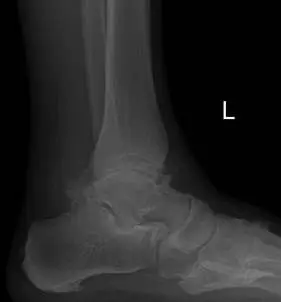

Ankle joint replacements are a reserved procedure for patients who meet certain criteria for functionality involving age, medical conditions, level of arthritis, and activity level, amongst others. The level of arthritis is typically severe and dibilitating as demonstrated in the x-ray image below. This person had a severe ankle fracture many years ago that was surgically repaired and later developed limiting arthritis to the point where they could no longer use their ankle because of pain. There is absence of joint space at the ankle joint along with remodeling of the bones around the ankle due to degeneration of the joint. The abnormal appearance of the thin bone called the fibula is a result of not fixing this bone when the patient had the original surgery.  This is referred to as malunion.